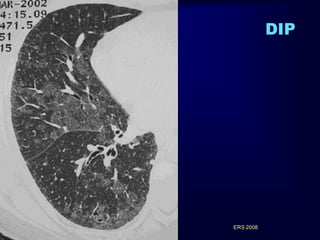

DIP • • • • • 90% of patientswith DIP smoked or had smoked cigarettes onset of symptoms : ~ 40 yrs dyspnoea and cough male predominance: 2>1 inspiratory crackles : 60% digital clubbing :50% RARE DISEASE Hartman et al Radiology 1993 (n=22 from 5 centers) -in children DIP it is probably a different disease not related to smoking -DIP also occurs in non-smokers (of 40 cases of Carrington et al: 10%) -association with systemic disorders or infections -DIP element (focal pigmented macrophage accumulation) histologically ERS 2008 in all smokers - “DIP-like reaction”

GROUND GLASS: PREVAILING FEATURE ERS2008 GGO in: Outpatients with Slowly Progressive Dyspnea

DIP Typically: subpleural /lowerlung zones Reticulation seen in ~40-50% Honeycombing NOT significant ERS 2008